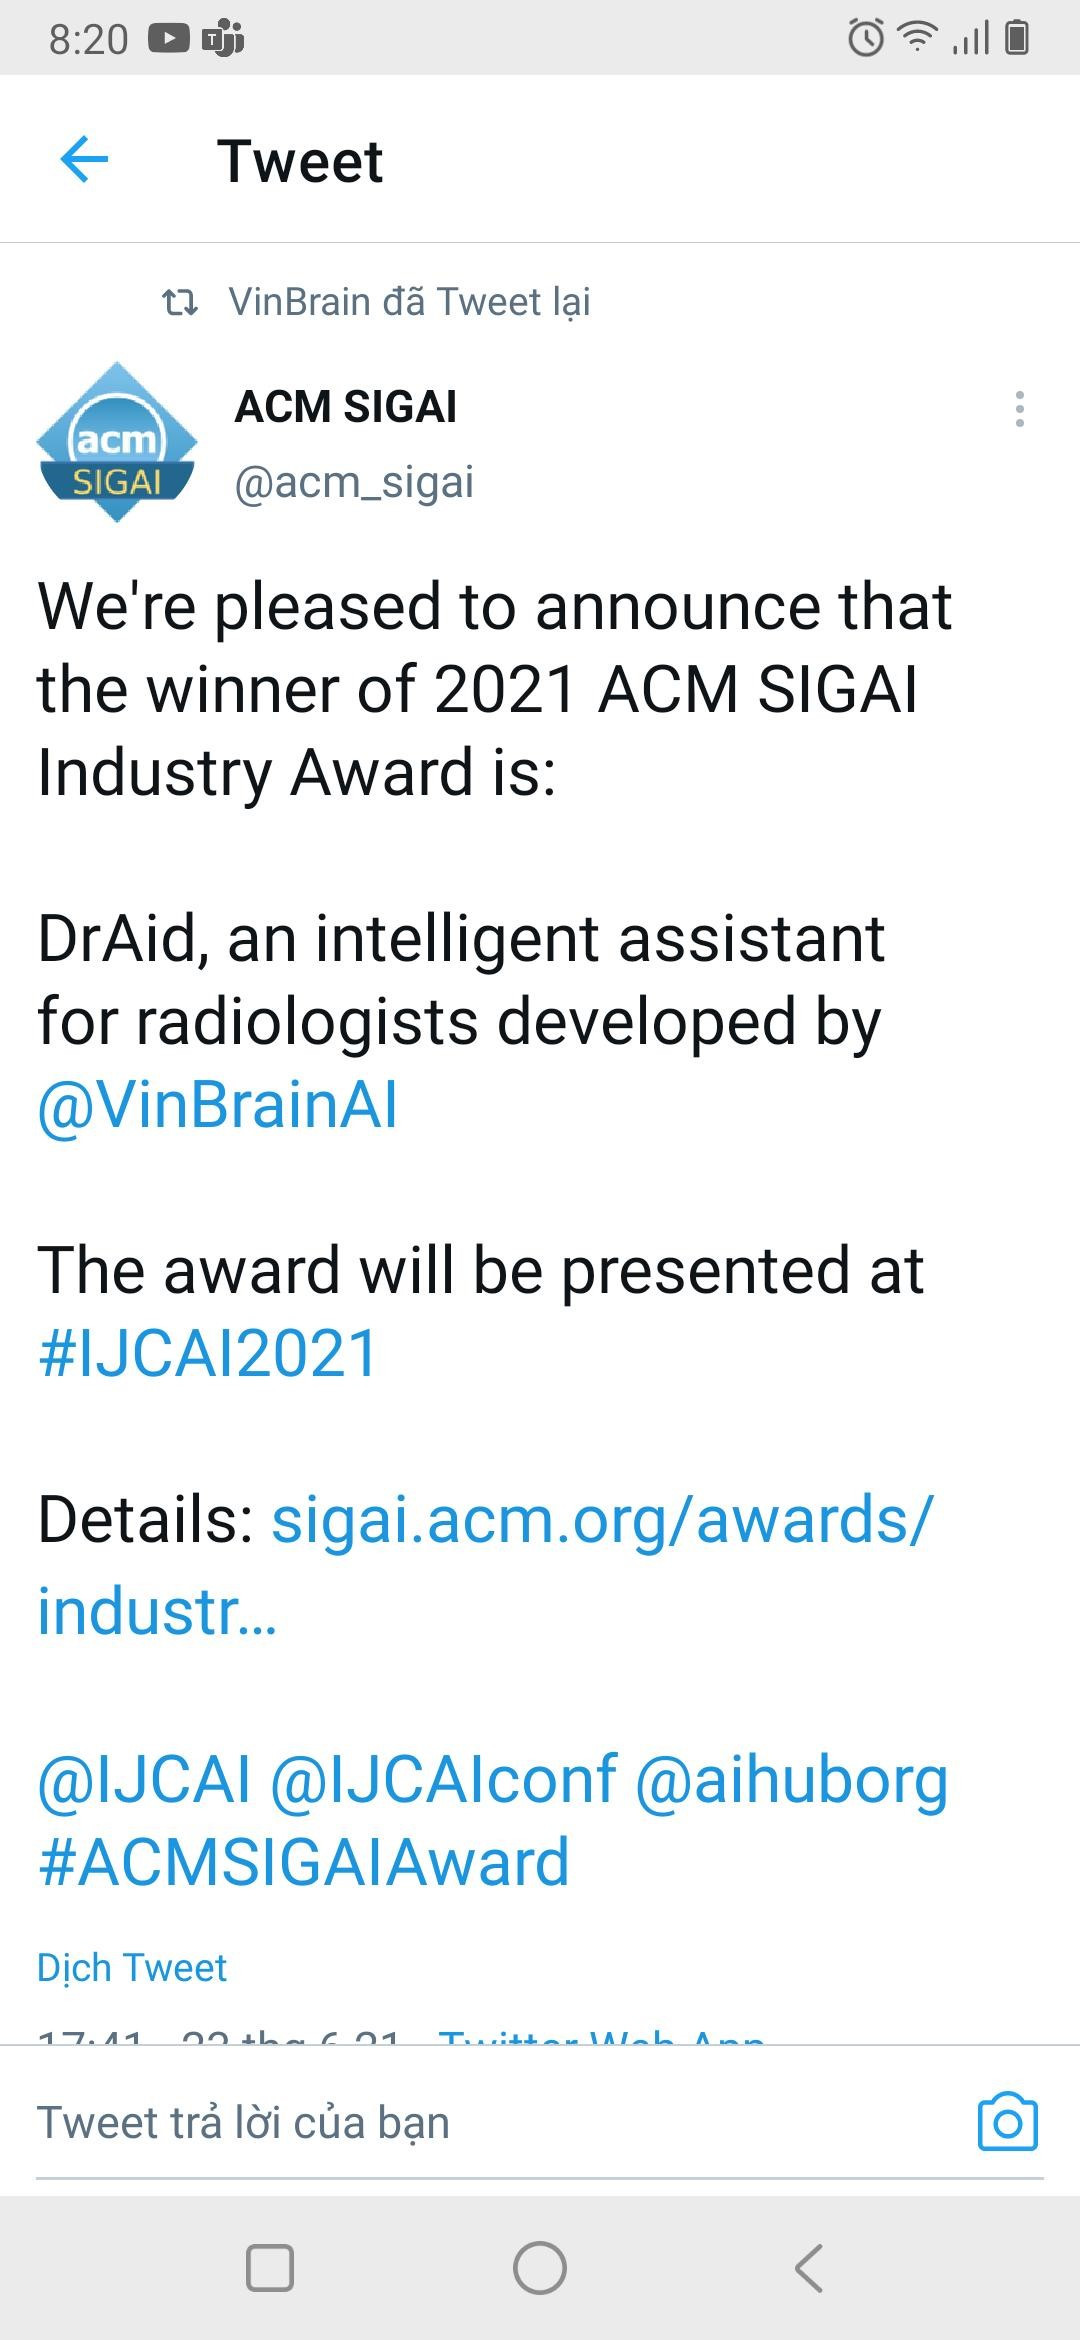

Tài liệu cung cấp thực trạng chẩn đoán lao hiện tại; đồng thời giới thiệu mô hình AI chẩn đoán và tầm soát bệnh lao phiên bản đầu tiên với độ nhạy 86% và độ đặc hiệu lên đến 96,1 %.

Nhằm nâng cao hiệu quả chẩn đoán và điều trị bệnh lao, VinBrain và FIT - Tổ chức phi chính phủ của Đức hoạt động trong lĩnh vực phòng và chống lao đã hợp tác biên soạn và phát hành sách trắng.